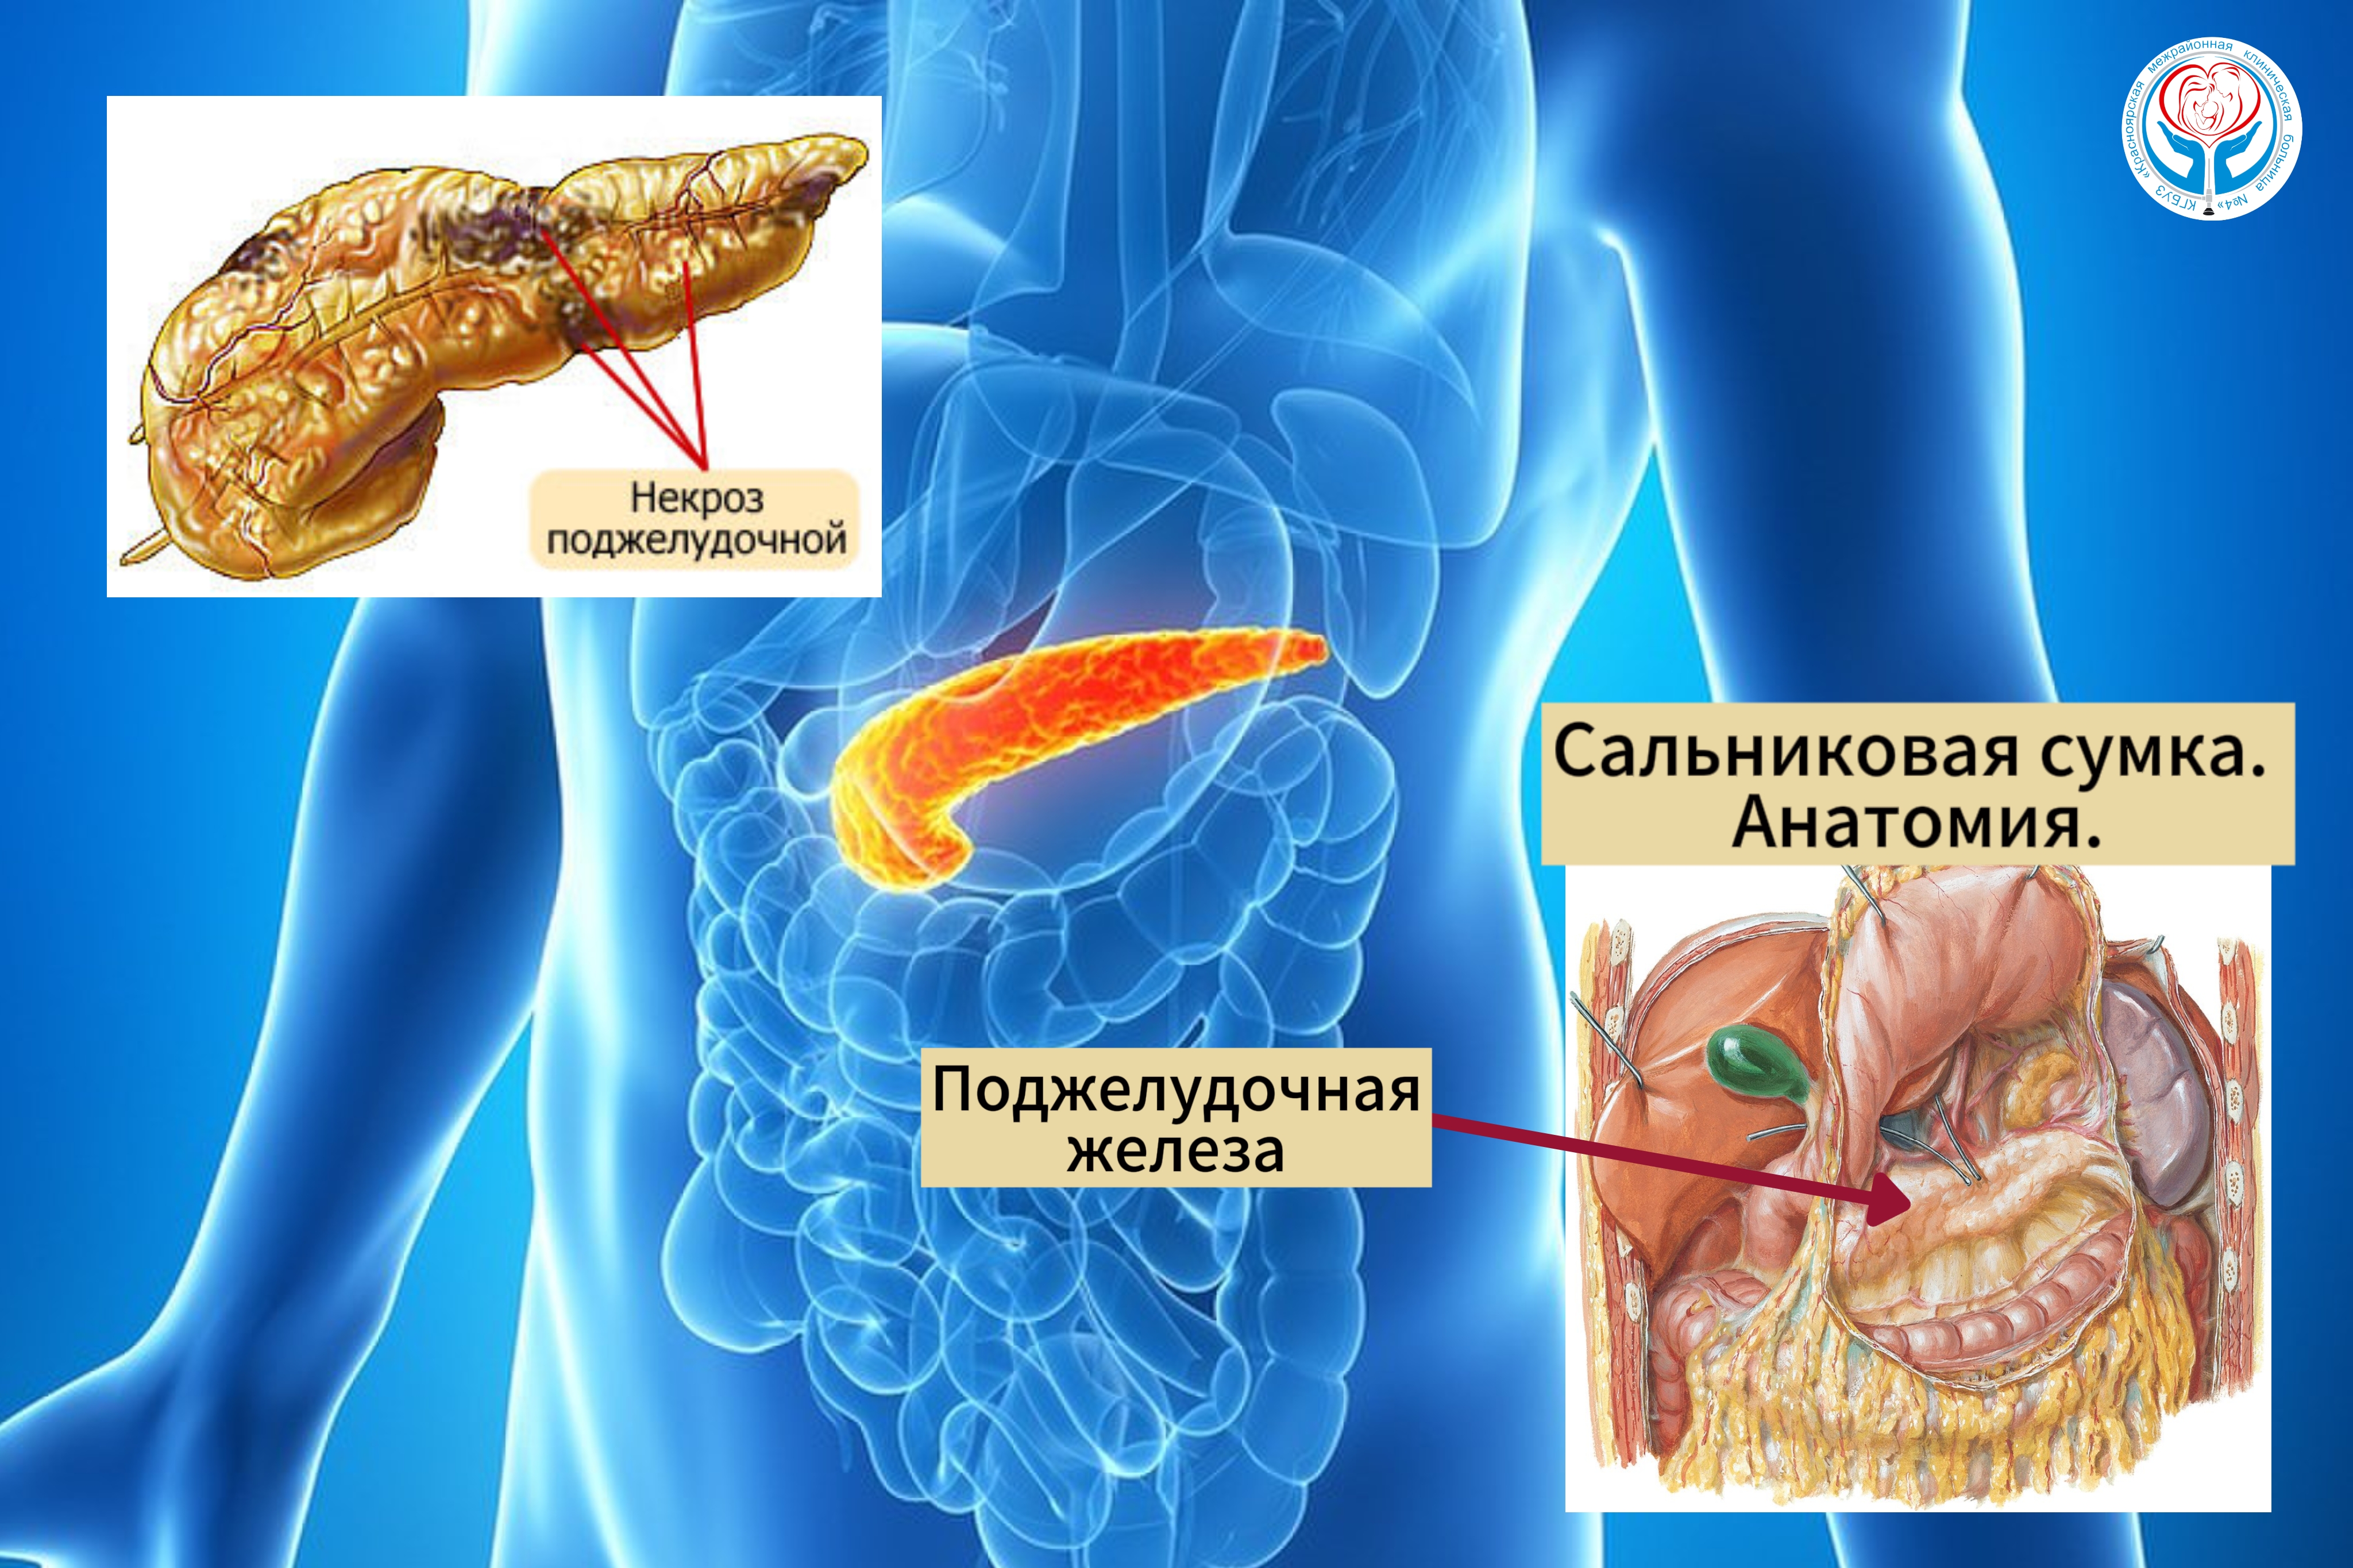

05.03.2024

Врачи Больницы на Кутузова спасли пациента в крайне тяжёлом состоянии с диагнозом панкреонекроз

Дважды спасённый: врачи КГБУЗ "КМКБ № 4" во второй раз спасли пациента с тяжёлым диагнозом

Подробнее...